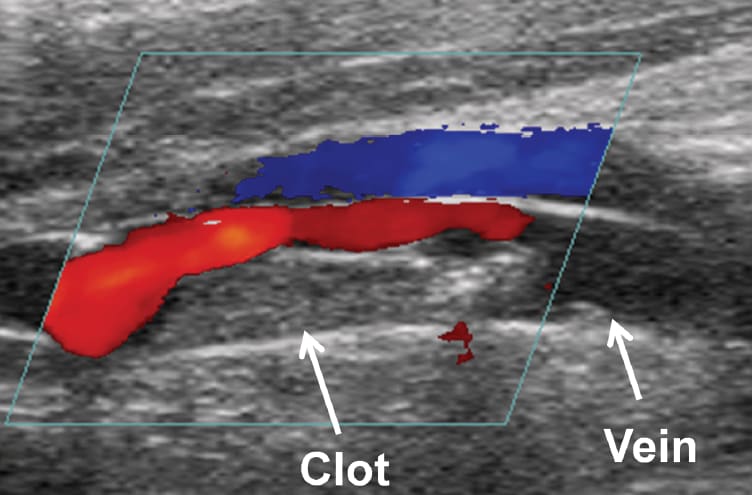

In the histotripsy system, an imaging transducer is closely aligned with the cloud-generating therapy transducer. This allows researchers to view microbubble cloud activity as it occurs. “We can see in real time when the cloud is generated, if it’s working, and if it has been effective in breaking up the clot,” says Xu. They also use color Doppler imaging to assess improvements in blood flow during the process.

“In these cases, it is difficult to differentiate between the clot and the vessel wall [because the clot has grown into the vessel wall],” says Xu. In this situation, the goal of the histotripsy is to create a channel through which the blood can flow rather than trying to fragment the entire clot. In preliminary animal studies, histotripsy did create a flow channel but required longer treatment times.